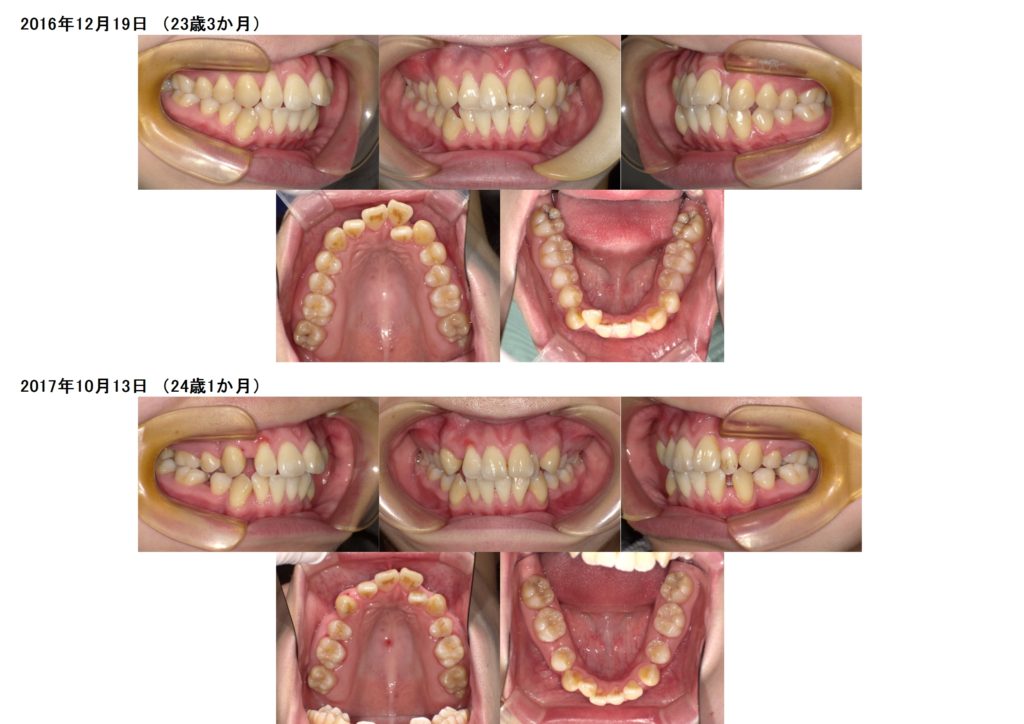

↑10歳8か月で来院された患者様ですが、ほぼ永久歯が生えそろっている状態です。

上下のスペースが不足しているので、残された成長を利用して上下の顎を広げる装置を入れ広げた状態です。